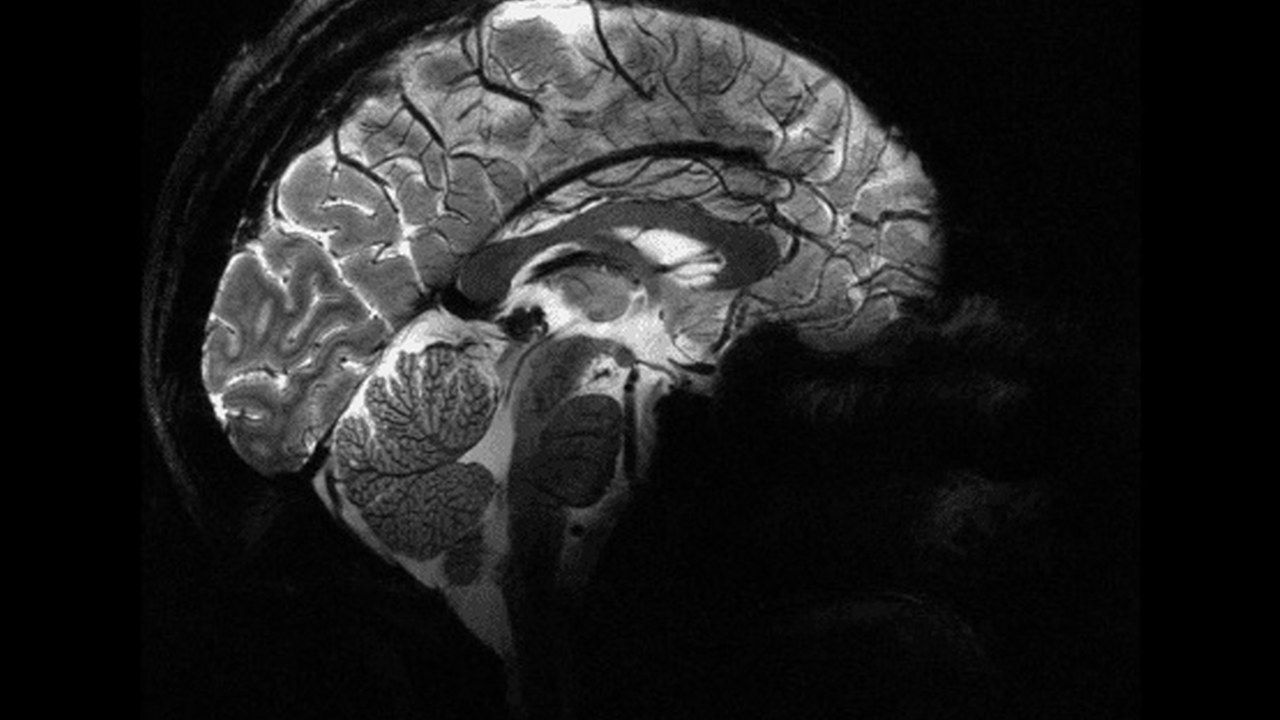

Bu olağanüstü hikâye, yıllar önce kimliği bilinmeyen bir Fransız adamın sağlık durumu üzerine yapılan araştırmalarla başladı. 44 yaşındaki adam, bacağında güçsüzlük hissi yaşadığı için doktora başvurdu. Yapılan muayenede, beyninin büyük bir kısmının kayıp olduğu ve kafatasının sıvı ile dolduğu ortaya çıktı. Bu duruma, tıbbi literatürde hidrosefali adı veriliyor; yani beynin büyük bir kısmının sıvı ile yer değiştirmesi. Ancak bu eksiklik, adamın günlük yaşamını herhangi bir şekilde etkilemedi.

Beyin taramalarında adamın beyninin büyük bir kısmının sıvı ile dolmuş olduğu ve tahrip olduğu tespit edilse de, yaşam kalitesinde herhangi bir belirgin azalma gözlemlenmedi. Bilişsel psikolog Axel Cleeremans, bu kişinin normal bir hayat sürdüğünü, ailesi olduğunu ve bir işi bulunduğunu belirtti. Yapılan IQ testi ise adamın 84 olduğunu gösterdi. Bu, normalin biraz altında bir seviyeye işaret ediyor ancak adamın yaşamını etkilemediği görüldü.